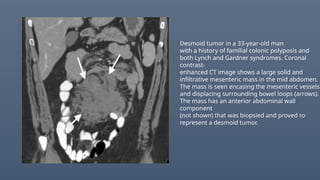

Desmoid tumor in a 33-year-old man

with a history of familial colonic polyposis and

both Lynch and Gardner syndromes. Coronal

contrast-

enhanced CT image shows a large solid and

infiltrative mesenteric mass in the mid abdomen.

The mass is seen encasing the mesenteric vessels

and displacing surrounding bowel loops (arrows).

The mass has an anterior abdominal wall

component

(not shown) that was biopsied and proved to

represent a desmoid tumor.